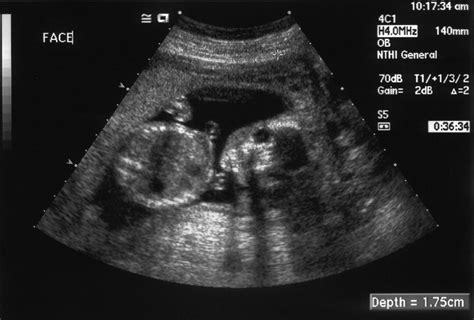

Kritickým faktorom je aj stará jazva po cisárskom reze. Ak žena otehotnie príliš skoro po sekcii, nápor nového tehotenstva by nemusela jazva vydržať a hrozí jej pretrhnutie. „Klinické skúsenosti ukazujú, že interval medzi cisárskym rezom a následnou tehotnosťou je dôležitý. Riziko pretrhnutia maternice je trikrát vyššie, ak je interval kratší ako osemnásť mesiacov. Ak odstup dodržíte, môžete skúsiť rodiť prirodzene,“ hovorí MUDr.Vladimír Cupaník. Na sonografi cké meranie jazvy sa pritom netreba spoliehať. „Neexistujú relevantné údaje o ultrazvukovom meraní hrúbky steny maternice.“ Aby sa predišlo pretrhnutiu, často sa tieto tehotenstvá ukončujú predčasne.